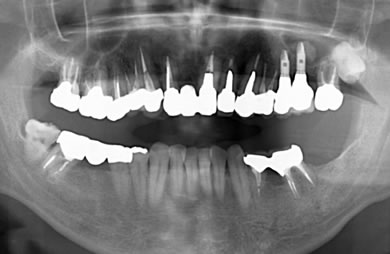

骨再生インプラント治療+セラミック治療

| カテゴリー | 【インプラント治療】【セラミック治療】 | ||||||||||||||||||||||||||||||||

| 治療方針 | ソケットリフト法により上顎洞底部を挙上することにより、骨の無い部分に骨をつくってあげ、インプラント治療を可能にする。 | ||||||||||||||||||||||||||||||||

| 治療内容 | インプラント2本(ソケットリフト)、メタルボンドセラミック5本、ハイブリッドセラミック2本 | ||||||||||||||||||||||||||||||||

| 総治療費 | 1,355,300円 | ||||||||||||||||||||||||||||||||

| 治療期間 | 海外から9ヶ月 |